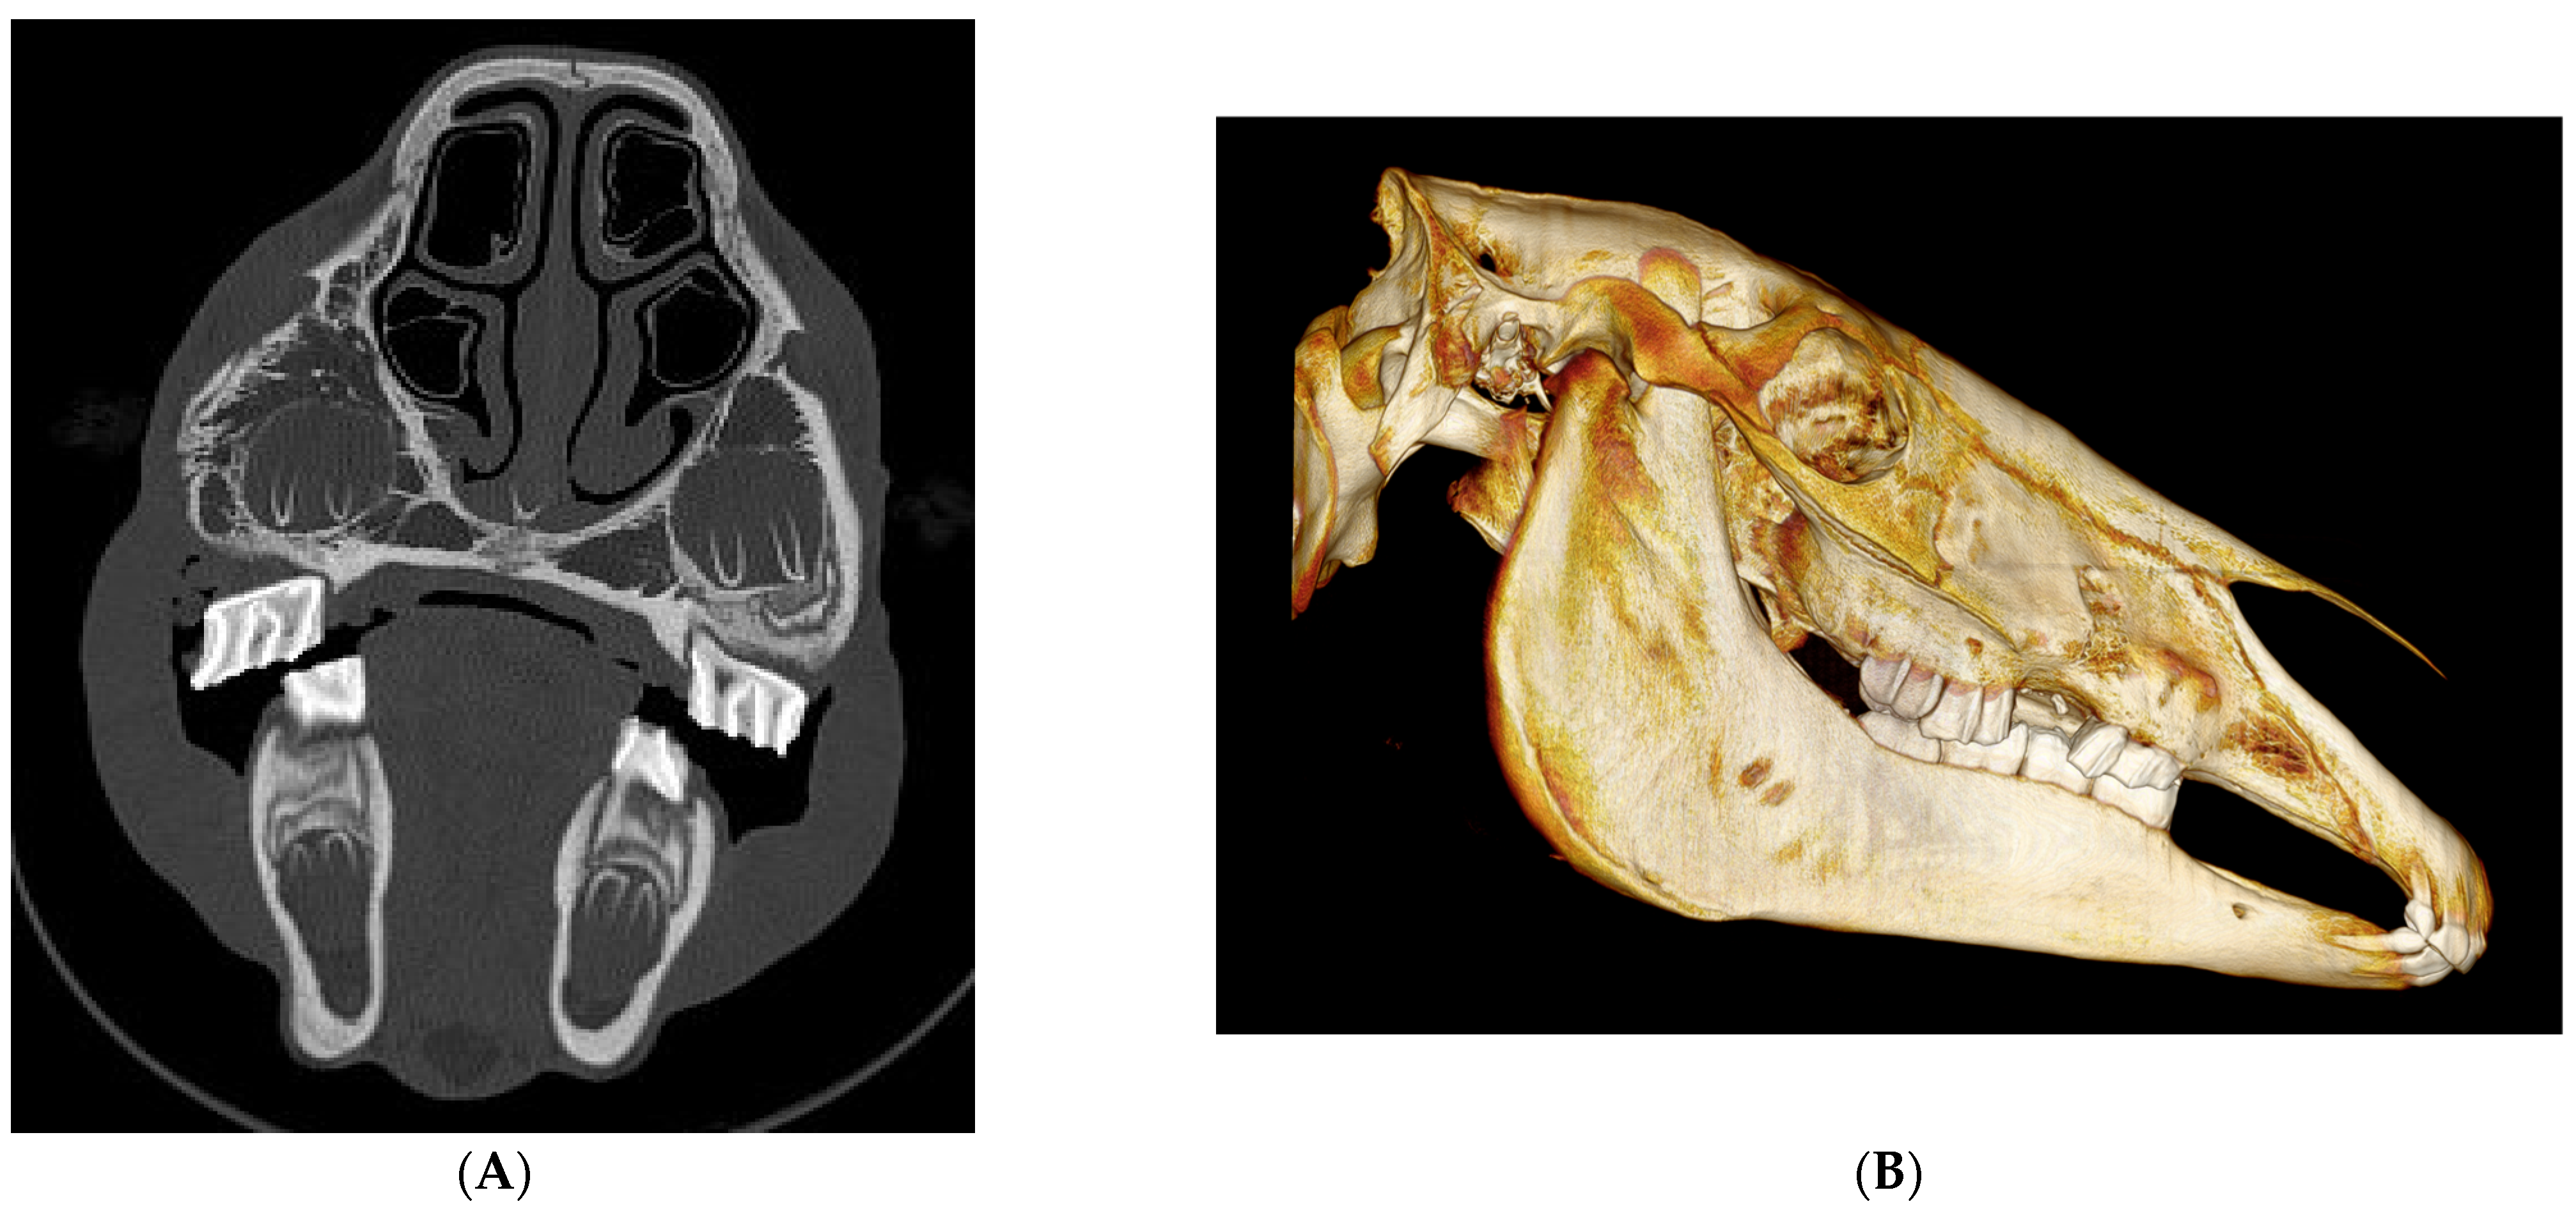

| 1 | 5 yo, G, WB | Unilateral Closed | Maxillary | Conservative | No | No | Good | |

| 2 | 18 yo, G, Unknown | Unilateral Closed | Maxillary | Maxillary Sinus Ventral conchal sinus Nasolacrimal duct | Conservative | No | No | Good |

| 3 | 12 yo, G, WB | Unilateral Open | Maxillary | Caudal maxillary sinus Nasolacrimal duct Root fracture 210 | Sinoscopy Bone fragment removal | No | No | Good |

| 4 | 9 yo, G, WB | Unilateral Open | Frontal Lacrimal Maxillary Nasal | Conchofrontal sinus Orbit Retrobulbar fragments | Sinoscopy | Yes | Sequestrum | Good |

| 5 | 12 yo, M, Polo Pony | Bilateral Closed | Nasal Frontal | Maxillary, conchofrontal, ventral conchal sinus Orbit Nasal septum collapse | Conservative | Yes | Narrowing left conchofrontal sinus Cosmetic | Fair to Good |

| 6 | 17 yo, M, Welsh | Bilateral Closed | Frontal Nasal Lacrimal | Caudal maxillary, dorsal conchal sinus Suture periostitis | Conservative | Yes | Suture periostitis Cosmetic | Fair to Good |

| 7 | 14 yo, M, TB | Unilateral Open | Nasal | Sinusitis dorsal conchal sinuses | Bone fragment removal Sinus Flush | No | Wound dehiscence | Good to Excellent |

| 8 | 2 months, filly, WB | Unilateral Open | Maxillary | Fracture tooth 507 | Fragment removal PMMA packing | Yes | Granuloma socket 507 | Excellent |

| 9 | 12 yo, G, WB | Unilateral Open | Maxillary Zygomatic | Maxillary and ventral conchal sinusitis fracture 210 Infraorbital canal | Sinoscopy fragment removal | Yes | No | Good |

| 10 | 5 yo, M, WB | Unilateral Closed | Maxillary Nasal Frontal Lacrimal | Orbit Rostral maxillary/ventral conchal sinusitis | Conservative | No | No | Excellent |

| 11 | 7 yo, G, WB | Bilateral Closed | Nasal | Suture periostitis Nasolacrimal duct | Conservative | No | No | Good |

| 12 | 7 yo, S, Lusitano | Unilateral Open | Nasal Maxillary Incisive | Rostral maxillary and ventral conchal sinusitis | Conservative | Yes | No Cosmetic | Good |

| 13 | 15 yo, G, WB | Unilateral Closed | Maxillary Nasal | Periapical infection 106, 107 and 108 | Oral extraction 106, 107 and 108 | No | Orocutaneous fistula | Fair |